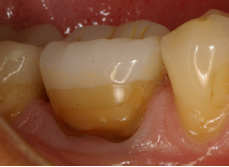

EC en #34 a los 19 años (IPS-Empress). El ionómero de vidrio en gingival tiene una longevidad de 23 años y debe repararse.

Control radiográfico a los 19 años.